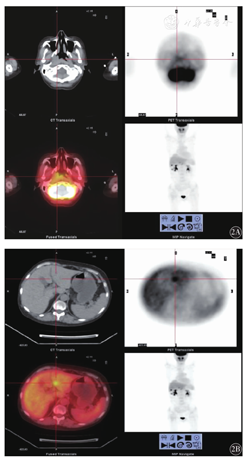

18F-FDG PET-CT检查后,20.6%(28/136)患者的临床分期上调,2.9%(4/136)下调(表2)。其中,由增强CTⅠ期变成18F-FDG PET-CTⅡ期8例,为18F-FDG PET-CT发现除CT报告以外的同侧直径<1 cm的肿大淋巴结,且摄取较正常组织升高;Ⅰ期变成Ⅲ期2例,为18F-FDG PET-CT发现腹膜后较小且摄取增高的淋巴结;Ⅱ期变成Ⅲ期12例,为18F-FDG PET-CT于纵隔两侧发现代谢增高的淋巴结;Ⅱ期变成Ⅳ期2例,为18F-FDG PET-CT发现肝脏占位且代谢升高,结外器官受侵;Ⅱ期变成Ⅰ期2例,为18F-FDG PET-CT发现受侵淋巴结区未见代谢增高,考虑炎性增大淋巴结;Ⅲ期变成Ⅳ期4例,因18F-FDG PET-CT发现了肝脏及肺部淋巴瘤浸润性病灶且伴代谢增高;Ⅳ期变成Ⅲ期2例,均为18F-FDG PET-CT判断肺以及肝脏为良性病变,不存在高代谢,不考虑淋巴结浸润,且结合后期临床资料,排除受侵。分期改变后,16例(11.8%)患者调整了治疗方案、治疗周期及放疗范围。典型病例:1例Ⅱ期变成Ⅳ期的患者,行常规CT检查提示鼻咽部右后壁增厚,腮腺区、双侧腋窝、双侧腹股沟淋巴结肿大,肝脏未见病灶;后行18F-FDG PET-CT检查提示鼻咽腔右侧壁软组织增厚,FDG代谢增高,SUVmax 2.08,双侧腋窝多发淋巴结肿大,较大淋巴结有FDG轻度增高,SUVmax 0.69,肝脏多发结节,FDG代谢异常增高,SUVmax 5.8,考虑有活性的肿瘤组织存在,肝脏受侵;后经临床随访,化疗后病灶明显缩小,临床诊断HL肝脏受侵,分期上调为Ⅳ期,并因此改变了治疗方案(图2)。